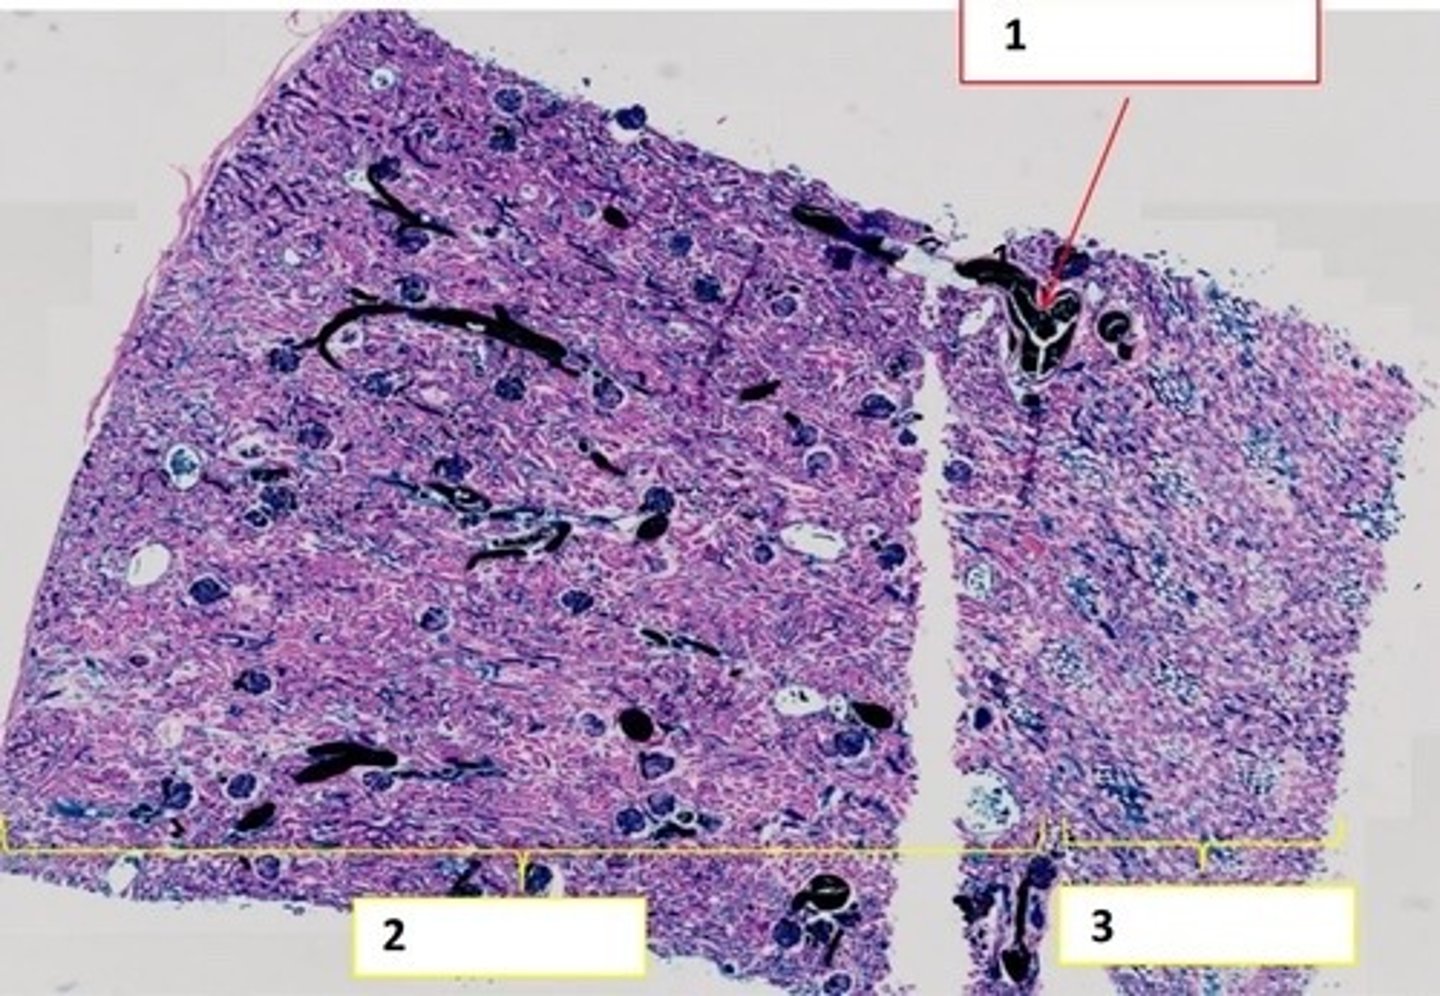

Wątroba ludzka (H+E)

Wątroba ludzka (met. Mallory)

Wątroba - komórki Browicza-Kupffera

(barw. błękitem trypanu)